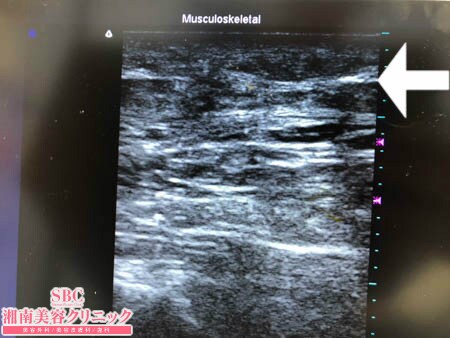

No.205592【脂肪吸引】【動画あり】湘南美容外科全ドクターの脂肪吸引最高責任者である竹田先生による脂肪吸引のフォトギャラリー!太ったから脂肪吸引を受ける!現役ナースさんの太ももを細くする!!術中3Dタッチビュー・左太もも後面

上の画像の通り。

しっかりと根こそがせてもらいました。